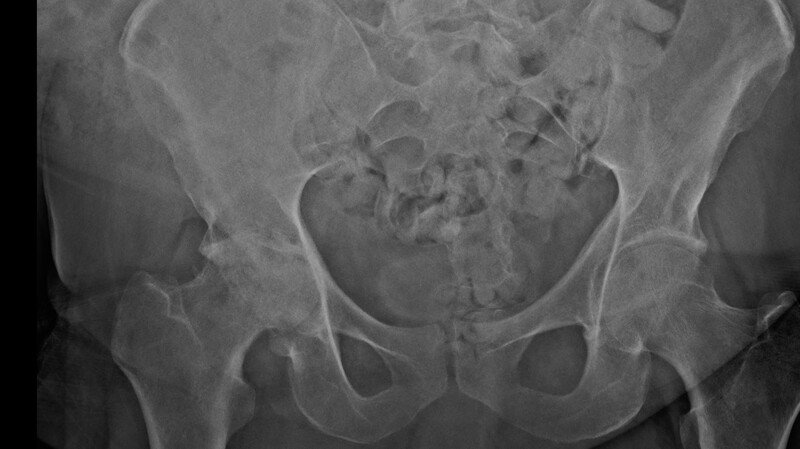

Desde 2024, sofro com um problema grave no quadril direito, diagnosticado como coxartrose acentuada. Um primeiro laudo médico já mostrava desgaste severo da articulação. Mesmo com acompanhamento e tratamentos, a doença continuou avançando.

Em dezembro de 2025, um novo exame realizado no Hospital Universitário Regional dos Campos Gerais confirmou a piora do quadro, passando a apresentar deformidade da cabeça do fêmur, além da perda quase total da articulação. Isso significa, na prática, que hoje convivo com dor diária intensa, dificuldade para caminhar, sentar, levantar e até dormir.

Os médicos indicaram como solução definitiva a cirurgia de prótese total de quadril, que pode me devolver a mobilidade e a dignidade. Porém, no momento, não tenho condições financeiras de arcar com todos os custos envolvidos no procedimento, exames, medicamentos e recuperação.